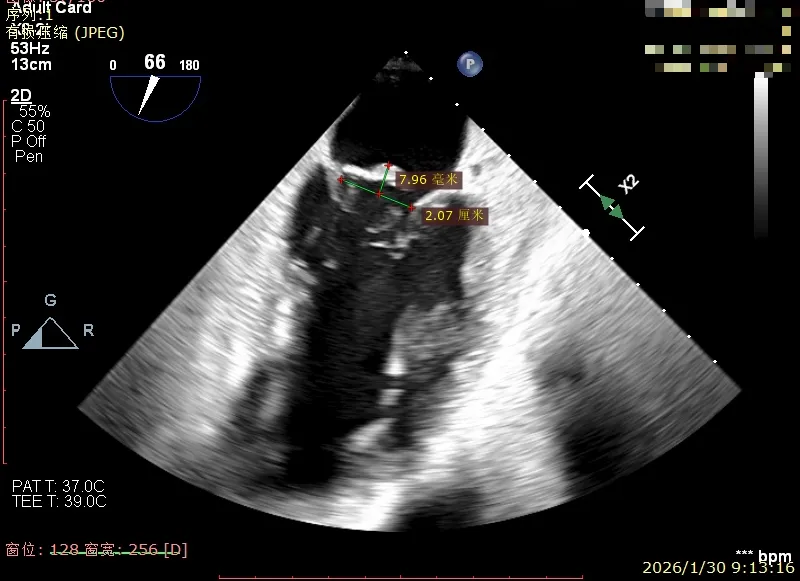

Flail宽度约21mm,Flail高度约8mm

3区前叶长度约22mm,后叶长度约11.6mm

2区前叶长度约32.2mm,后叶长度约16mm

2区Flail Gap约4mm